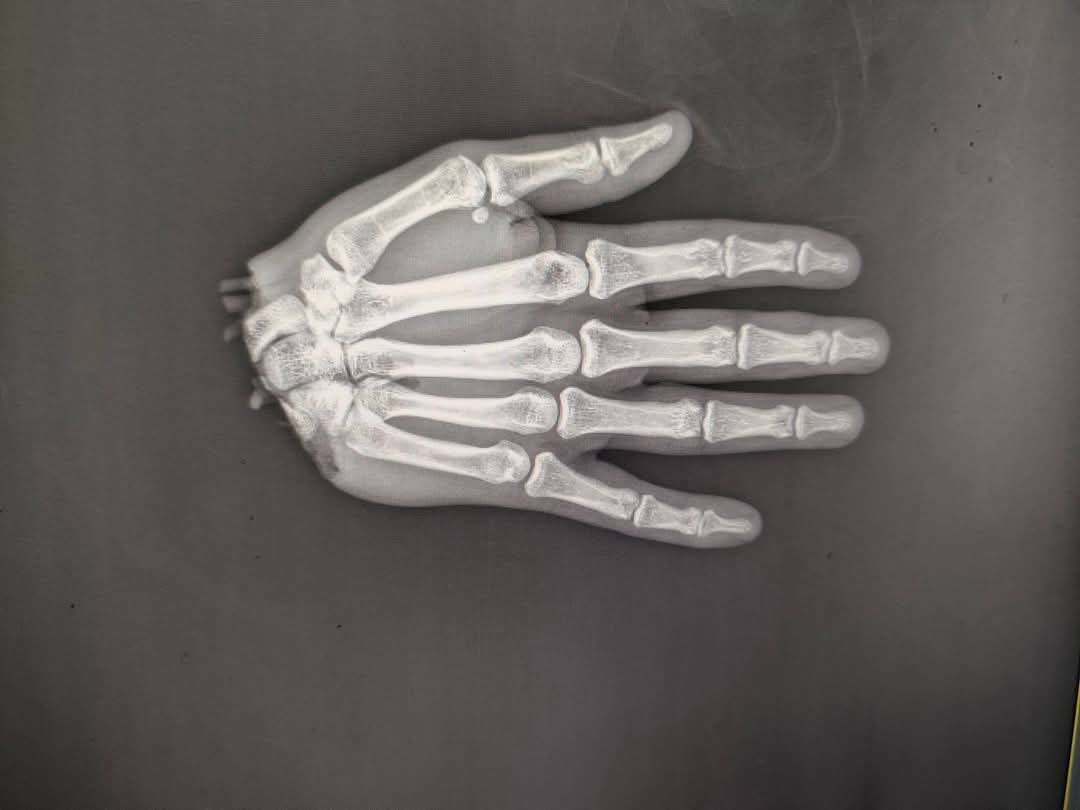

تمكن أطباء قسم جراحة التجميل بمستشفى سيد جلال الجامعي، من إجراء جراحة لإعادة يد شاب بعد قطعها في حادث سير.

وتابع: شاب صغير اتعرض لحادث مروع، لإيد اتقطعت بالكامل من عند الرسغ، وفي لحظ الحلم اتكسر، والأمل ضاع، والدنيا اسودّت،لكنهم والحمدلله في قسم جراحة التجميل – كلية طب الأزهر، ما بيعرفوش كلمة مستحيل، نواب جراحة التجميل بالأزهر دخلوا في سباق مع الزمن، الحاله اتحجزت ودخلت علي عمليات الطوارئ في أقل من نص ساعة، وتم إجراء عملية دقيقة جدًا، وصلوا فيها شرايين، أوردة، أعصاب، أوتار، عضلات، كله اتوصّل بإتقان، وكأن الإيد عمرها ما اتقطعت.